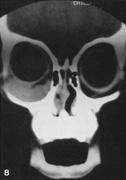

Although intraconal lesions medial to the nerve sometimes can be approached laterally, great care to identify and protect the optic nerve is required during deep orbital dissection. Because the eyelid crease incision allows such wide exposure of the superolateral orbit, it is often possible to remove fairly large orbital lesions without removing the lateral orbital wall (Fig. 9). Surgery in this case proceeds as described to exposure of the superior and lateral bony orbital rims. It is not necessary to reflect periosteum over the external surface of the rim. Instead, once periosteum at the rim is exposed, it is cut with cautery and then only the mesial periorbita need be elevated internally to expose orbital contents with subsequent intra-orbital dissection carried out with the lateral rim in place. Often it is preferable to initially attempt to remove intraconal or lacrimal fossa lesions in this fashion. If exposure proves inadequate, the periosteum over the external surface of the lateral orbital rim can be elevated and osteotomies and removal of the lateral wall still can be carried out.

Fig. 9. A,B. Coronal and axial CT images of a large intraconal neoplasm. C. Because it was felt to represent a well-encapsulated cavernous hemangioma, this lesion was a candidate for removal via an eyelid crease orbitotomy without bone removal. The eyelid crease incision marked. D. Incision made with scalpel. E. Orbicularis muscle is tented up and incised to expose the underlying septum. F. Dissection of a skin-muscle flap deep to orbicularis exposes the orbital septum and superior orbital bony rim. G. Cutting cautery is used to incise periosteum along the superior and lateral rims; finger palpation of the bone helps to direct this incision. H. Periorbita is elevated along the mesial surface of the lateral orbital rim in order to expose the deep orbital tissues. I. The cavernous hemangioma is visualized in the wound. Retraction is provided by one or more malleable retractors. J. Cryoprobe is affixed to the hemangioma to facilitate manipulation of the lesion. K. Large cavernous hemangioma after removal through the eyelid crease incision which was accomplished without bone removal. L. Periorbita is reattached over the lateral rim. M. The eyelid crease incision is closed with a running suture.